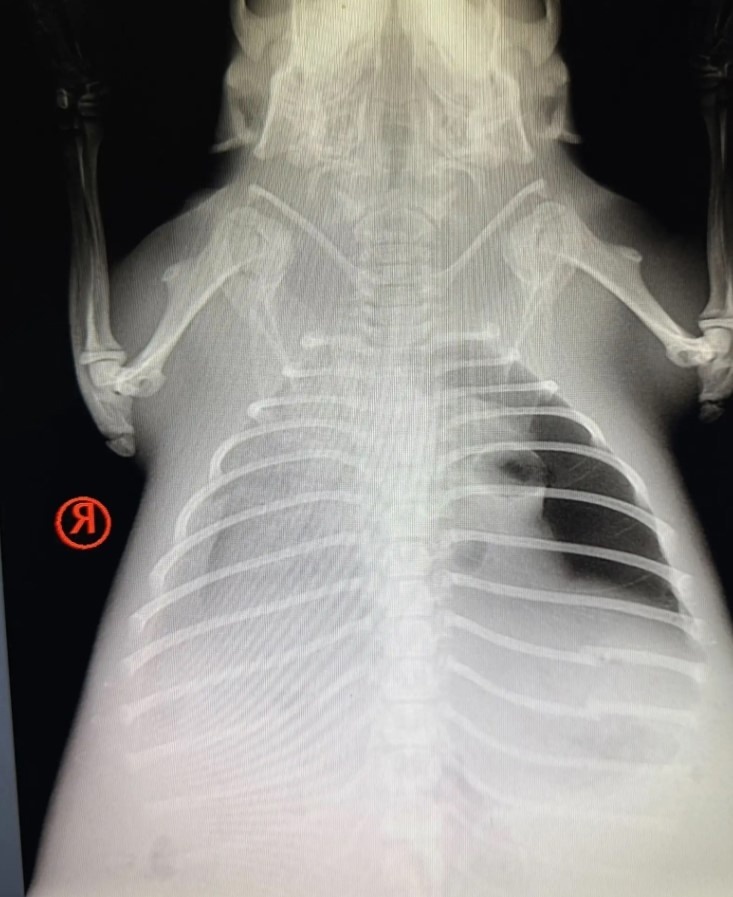

Диагноз: Травмы и Невидимый Враг

Первое, что бросилось в глаза специалистам – общее угнетенное состояние малышки. Но настоящие враги скрывались внутри. Тщательный ветеринарный осмотр выявил двойной удар:

1. Пневмония: Воспаление легких – серьезнейшее заболевание, особенно для маленького, ослабленного организма. Оно лишало ее сил и могло стать фатальным.

2. Внутренние повреждения: Судя по характеру травм, история сложилась трагично. Вероятнее всего, родную запруду бобренка прорвало мощным потоком воды (возможно, после сильных дождей или из-за деятельности человека). Малышка получила травмы в этом хаосе, была выброшена стихией на сушу и, дезориентированная, бродила в поисках спасения, пока силы не покинули ее на том самом поле.

Борьба за жизнь: Ветеринары диагностировали пневмонию и внутренние травмы. Началось срочное лечение антибиотиками и поддерживающей терапией.